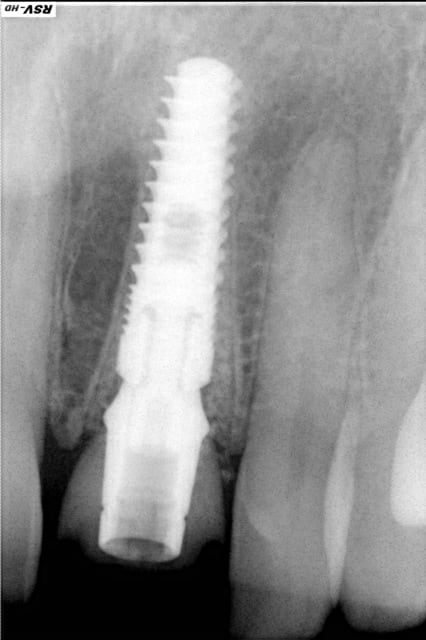

Voilà ce que l'on arrive à faire mais ce fut limite!

Interactive dx8dv8 - Eugenol